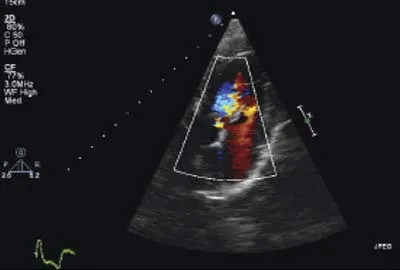

Imaging ResultsThoracic radiographs and abdominal ultrasound were unremarkable. Two-dimensional, M-mode, color flow, and spectral Doppler echocardiography demonstrated a vegetative lesion associated with the aortic valve, moderate aortic regurgitation, mild thickening of the mitral valve, and mild left atrial enlargement (Figures 1 and 2).

Figure 2 (below): Left parasternal long-axis view: Color flow echocardiography showed moderate aortic valve regurgitation.